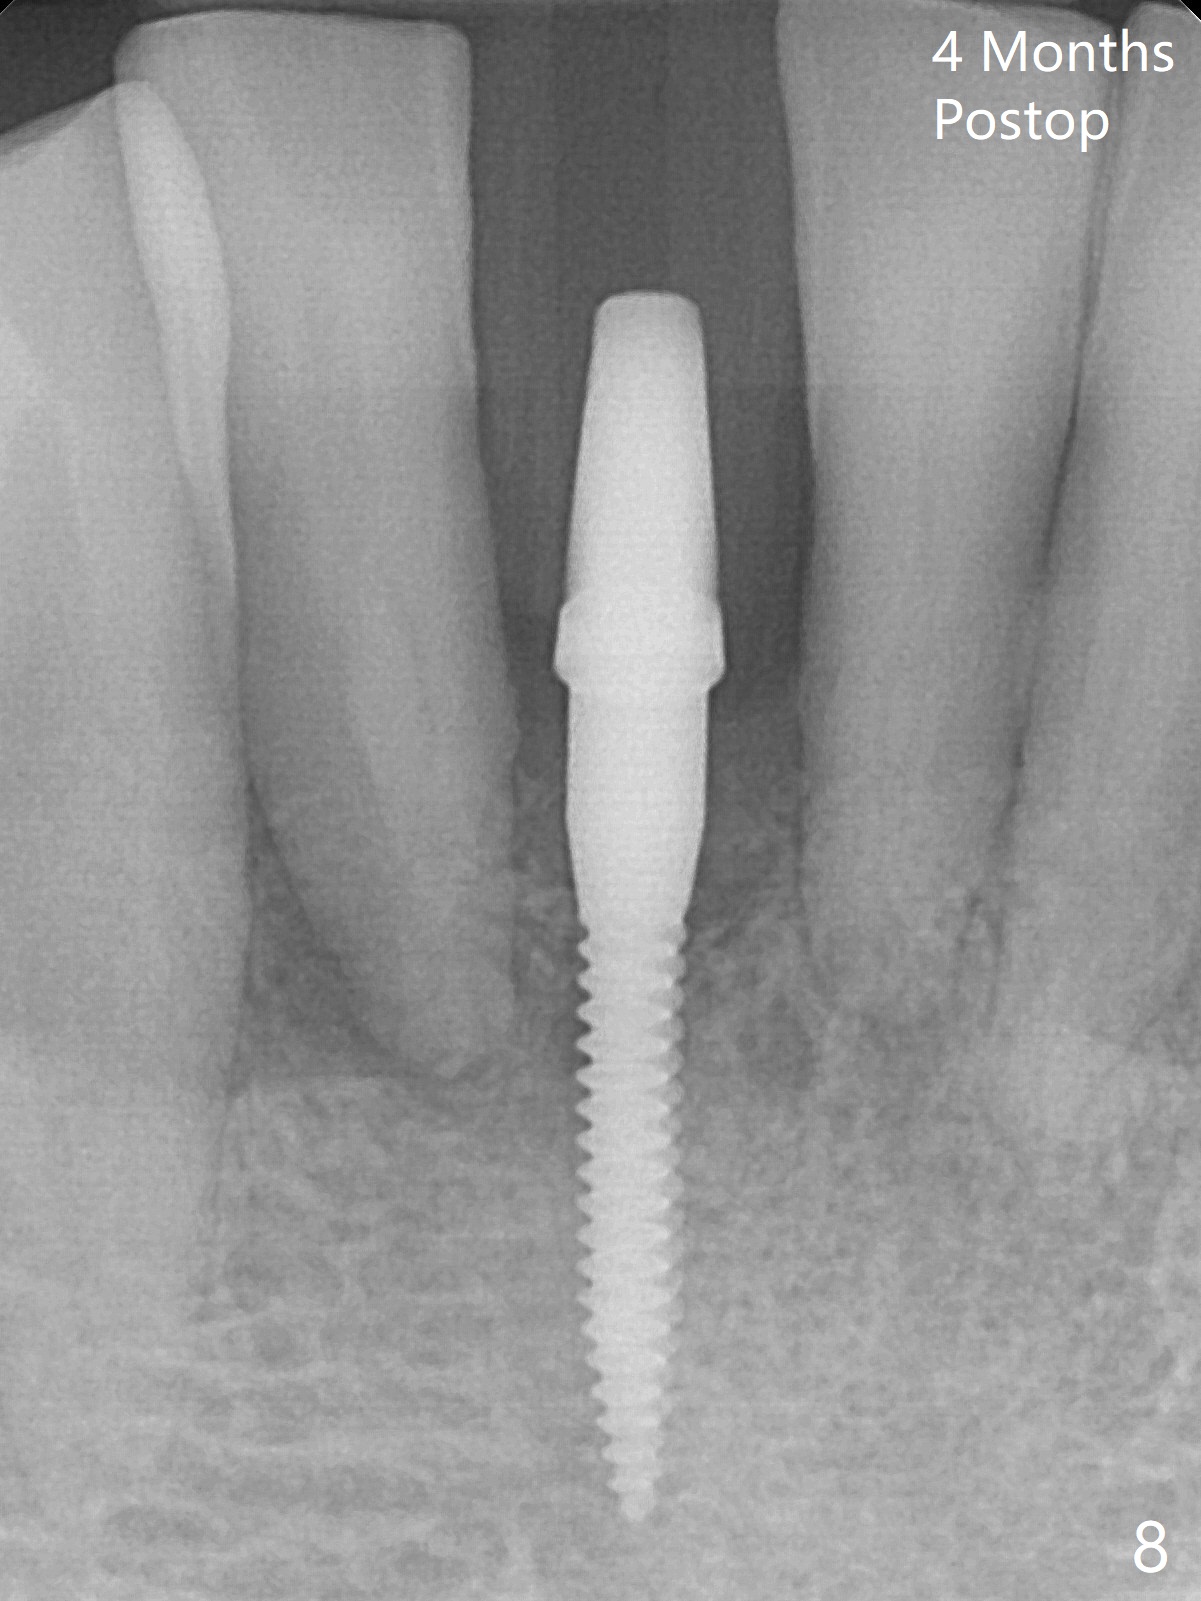

Out of financial concern, the patient does not agree to have the tooth #26 extracted. Due to atrophy of the most coronal ridge buccally at #25 (Fig.1,2 *), osteotomy is initiated difficult and distal (Fig.3). After 1.2 mm drill removal (Fig.3' black area), Lindamann bur is used to move the osteotomy mesial (red area). A 2x12(4) mm 1-piece implant is placed (Fig.4,5); the buccal defect is packed with allograft (Vanilla, .5-1 mm cancellous/cortical mixture, *). When the tooth #26 fails, a 2 mm implant will be placed (Fig.6 blue). Following abutment adjustment, a provisional is fabricated (Fig.7 P); note the lower incisal edges of #25 and 26, as compared to those of the neighboring teeth. To reduce occlusal trauma, the incisal edge of the tooth #26 has been decreased (Fig.5 open arrow). The implant threads seem not to be exposed 4 months postop (Fig.8), although the tooth #26 has mobility II.